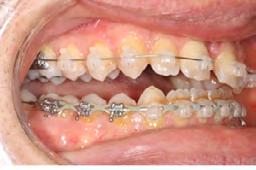

Clinical evaluation showed a mild Class III skeletal pattern with a constricted maxilla, mildly dolichofacial and straight

profile (Figure 1). Full adult dentition was present with all third molars extracted. Maxillary and mandibular incisors were normoclined. The maxillary midline coincided with the facial midline, and the mandibular midline was 2 mm to the right of the facial midline. There was a 2 mm to 5 mm lateral open bite on the right side from the second molar to the lateral incisor, and the maxillary occlusal plane was canted to the left of the interpupillary line. A lateral tongue thrust into the open bite was noted on swallow.

The right side was in posterior crossbite and there was an edge-to-edge anterior bite with wear on the maxillary central incisors. Mild gingival recession was noted, but soft tissue was generally within normal limits. CBCT analysis found no radiographic evidence of osteoarthritis in the TMJ joints, nor osseous or apical pathology involving the maxillary or mandibular teeth. His airway was not constricted. Initial report from the myofunctional therapist indicated that the patient never developed a mature swallow sequence and had a bilateral posterior tongue thrust.

Figure 1. Initial records.